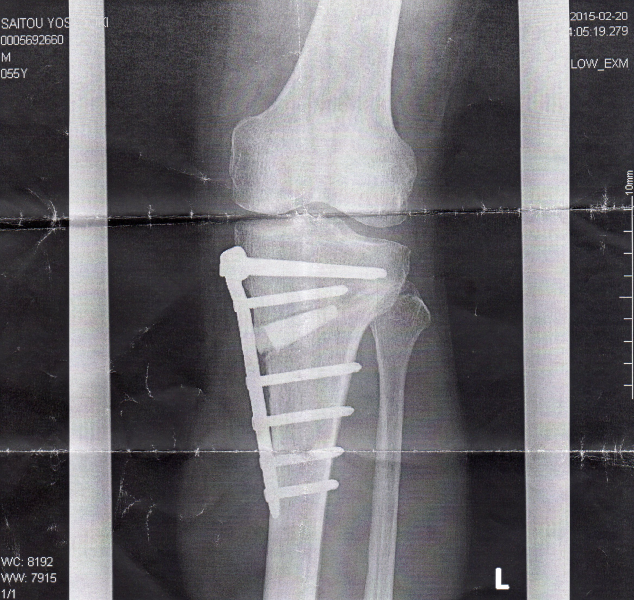

#記念に足のレントゲン写真(2015/2/20)をスキャナーで読み取っておきます。